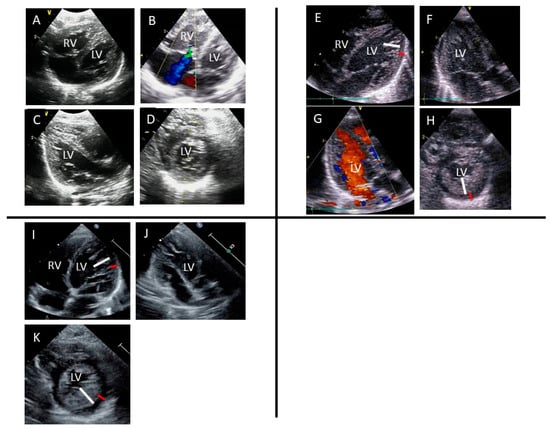

The patient harbored a novel heterozygous missense mutation (NM_000257.4:c.1090T>C, p.Phe364Leu) in the MYH7 gene (Figure 2). This mutation has not been previously reported in public databases of the general population, or is extremely rare, and it was predicted to be deleterious by multiple bioinformatics prediction tools (Table 1). ClinVar classified it as uncertain significance. According to the guidelines of the American College of Medical Genetics and Genomics and the Association for Molecular Pathology, the pathogenicity of this variant was considered likely pathogenic. It has been previously reported that the amino acid change Met362Arg in MYH7 includes all elements necessary for actin to move relative to myosin during adenosine triphosphate hydrolysis [11]. The patient’s father and brother also harbored the same mutation, and mild left ventricular noncompaction (LVNC) was demonstrated in them through echocardiography (Figure 2 and Table 2). For these reasons, we considered this novel mutation to be the cause of the patient’s condition.

The patient’s father and older brother had the same variant, and echocardiography showed that they had mild LVNC (Figure 2 and Table 2).

Figure 2. (A) The results of Sanger sequencing of target alleles (A: green, C: blue, T: red, G: black). (B) Family pedigree. E+ indicates variant positivity. Black color indicates that the patient is affected by LVNC.